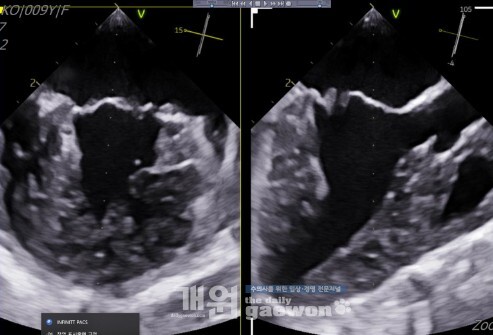

일반 심초 소견은 이러하다.

- ACVIM MMVD stage B2 w/ MVP & flail of A3

- LA/LV volume overload

- systolic myocardial dysfunction; mild

- TVI w/ PH (probability intermediate)

여기까지만 봤을 때는 피모벤단만 처방이 나가는 것, 리즈너블 하다고 생각할 수 있다. 그런데 같은 환자의 경식도 초음파 영상을 보자.

경식도 초음파 3D 영상

화살표 부분이 비어있다. 아직 많이 새진 않지만, 저기로 분명 역류가 올라오는 것이 확인되었다. 이 환자에서, MMVD 가 지금보다 진행되어서 판막륜이 좀 더 커진다고 상상하면, 저 비어있는 부분은 벌어지게 된다. 벌어지면 갑자기 엄청난 양의 역류가 올라올 것이다. 어느순간 갑자기 매우 나빠질 것이다.